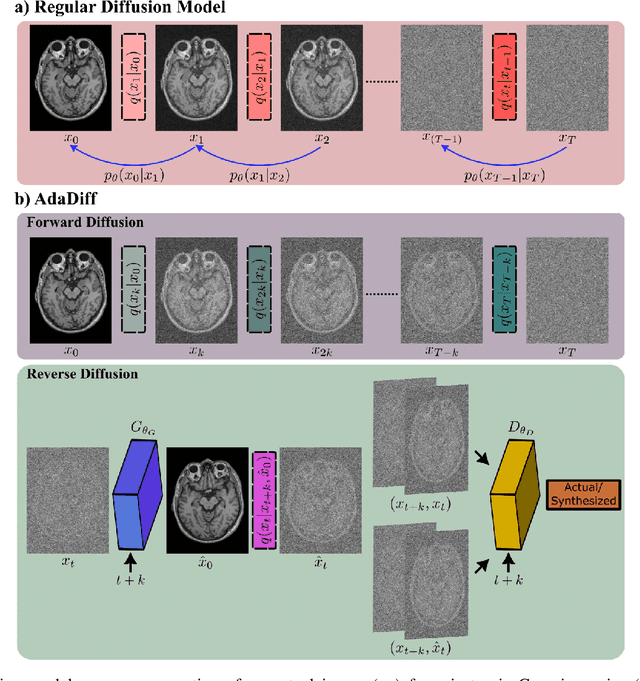

Abstract:Deep MRI reconstruction is commonly performed with conditional models that map undersampled data as input onto fully-sampled data as output. Conditional models perform de-aliasing under knowledge of the accelerated imaging operator, so they poorly generalize under domain shifts in the operator. Unconditional models are a powerful alternative that instead learn generative image priors to improve reliability against domain shifts. Recent diffusion models are particularly promising given their high representational diversity and sample quality. Nevertheless, projections through a static image prior can lead to suboptimal performance. Here we propose a novel MRI reconstruction, AdaDiff, based on an adaptive diffusion prior. To enable efficient image sampling, an adversarial mapper is introduced that enables use of large diffusion steps. A two-phase reconstruction is performed with the trained prior: a rapid-diffusion phase that produces an initial reconstruction, and an adaptation phase where the diffusion prior is updated to minimize reconstruction loss on acquired k-space data. Demonstrations on multi-contrast brain MRI clearly indicate that AdaDiff achieves superior performance to competing models in cross-domain tasks, and superior or on par performance in within-domain tasks.